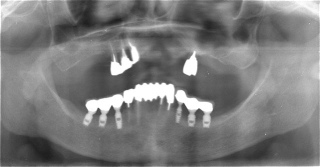

術前レントゲン

術後レントゲン